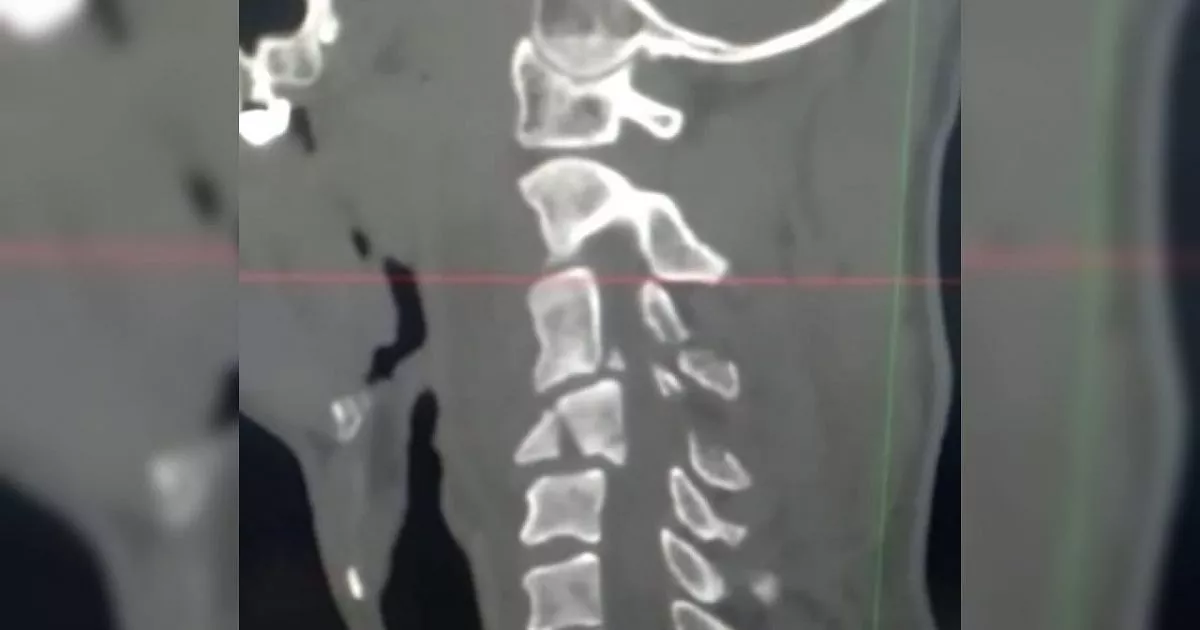

Ночью его доставили в Приемное отделение Городской больницы Новороссийска. Ему поставили диагноз - перелом 4-го шейного позвонка с нарушением проводимости по спинному мозгу. Состояние пациента было крайне тяжелым.

- Консервативные методы лечения бесперспективны, так как спинной мозг был сдавлен фрагментами разрушенного позвонка. Качество жизни больного снижалось с каждой минутой, представляя серьезную угрозу здоровью или даже жизни. После проведения необходимых диагностических исследований врачи принимают решение оперировать, - сообщается в Instagram городской больницы.

- Врачи удалили сломанный позвонок, сдавливающий спинной мозг, межпозвоночный диск, вместе с поврежденными связками и стабилизировали оперируемый сегмент при помощи кейджа. Кейдж представляет собой полый имплантат, который внутри заполняется измельченным костным составом разрушенного позвонка, - уточнили в больнице.